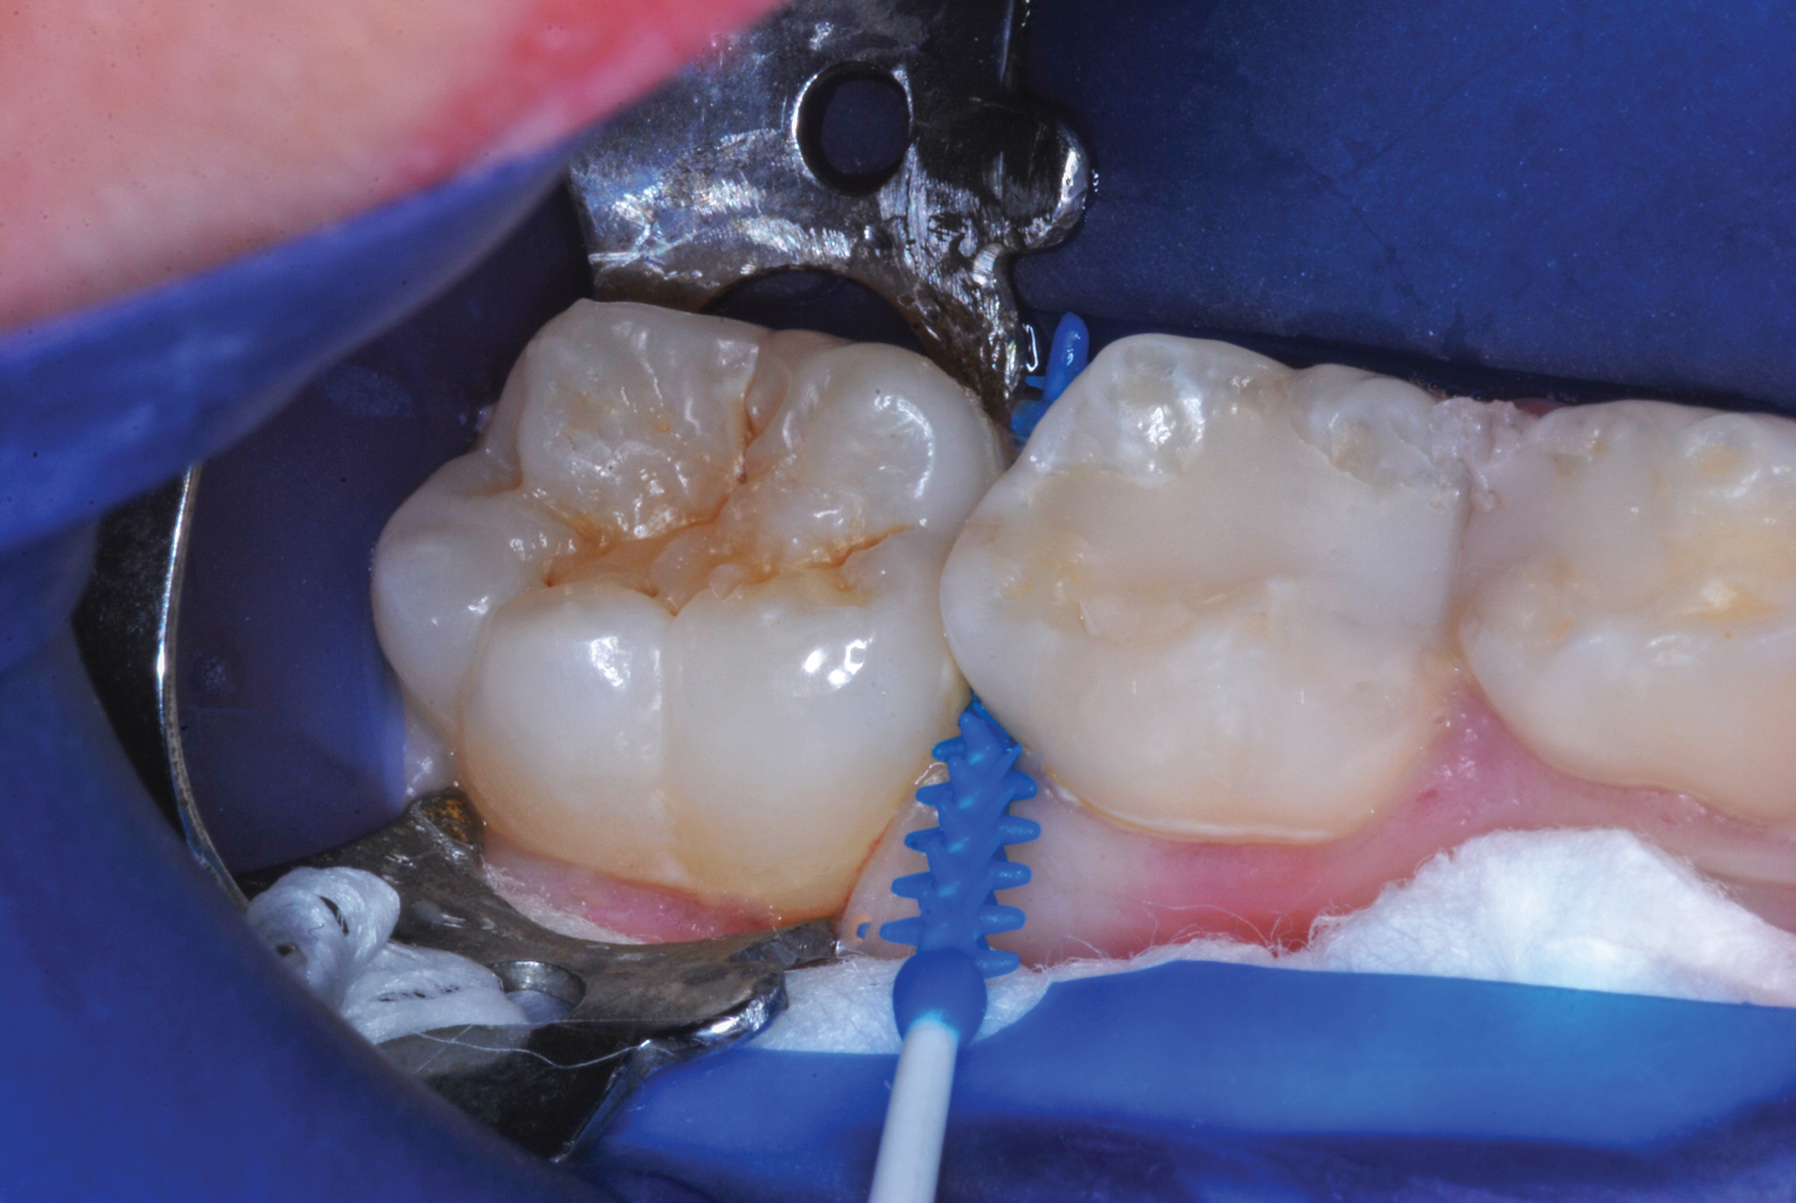

Fig 3. Three thin soft dental picks were used simultaneously for SDF proximal surface saturations in a teenaged patient (Fig 3). After 60 seconds, the treated regions were covered with 5% fluoride varnish (Fig 4). A comparison can be seen of pre-SDF-treatment bitewing films (Fig 5) and 8-month post-SDF bitewing films (Fig 6) for the patient shown in Fig 3 and Fig 4. Radiolucencies were similar or improved, except for contact of maxillary first and second molars.

Fig 4. Three thin soft dental picks were used simultaneously for SDF proximal surface saturations in a teenaged patient (Fig 3). After 60 seconds, the treated regions were covered with 5% fluoride varnish (Fig 4). A comparison can be seen of pre-SDF-treatment bitewing films (Fig 5) and 8-month post-SDF bitewing films (Fig 6) for the patient shown in Fig 3 and Fig 4. Radiolucencies were similar or improved, except for contact of maxillary first and second molars.

The authors' protocol for insertion of SDF-coated soft dental picks involves isolating the teeth with cotton rolls or other means, flossing the interproximal site to clear food debris and dental plaque, and then inserting a SDF-coated pick (Figure 1 and Figure 2) to saturate the contacting surfaces of the teeth with the fluid. This treatment is painless and requires no anesthetic. The pick should remain in place for at least 60 seconds and can be gently pulled in and out to agitate the fluid for enhanced surface coverage by capillary action. Additional SDF can be wiped on, using a small applicator, above the contact and in the buccal and lingual sluiceways. Excess fluid and any blood elicited may be blotted with a cotton swab. An additional 60-second insertion may be applied in the same way if there is radiographic evidence of a deeper decalcification or caries lesion. With the pick still in place, 5% (or 2.5%) fluoride varnish is painted over the treatment area, and the pick is then withdrawn.

Interproximal insertion of SDF is demonstrated in different patients in Figure 3 through Figure 11. Various diameters and brands of soft dental picks may be used depending on the closeness of the proximal surfaces and ease of insertion; for example, some picks are designed for use in wider spaces between teeth. This protocol also offers versatility. Figure 3, for example, shows the simultaneous use of three thin soft dental picks to saturate proximal surfaces with SDF in a teenaged patient; the treated regions were subsequently covered with fluoride varnish (Figure 4). This patient was initially treated in April 2019 (Figure 5), with an identical re-application 3 months later. As shown in Figure 6, the December 2019 bitewing film revealed good results with the possible exception of the contact regions of the maxillary first and second molars. New SDF application was completed in the December appointment.